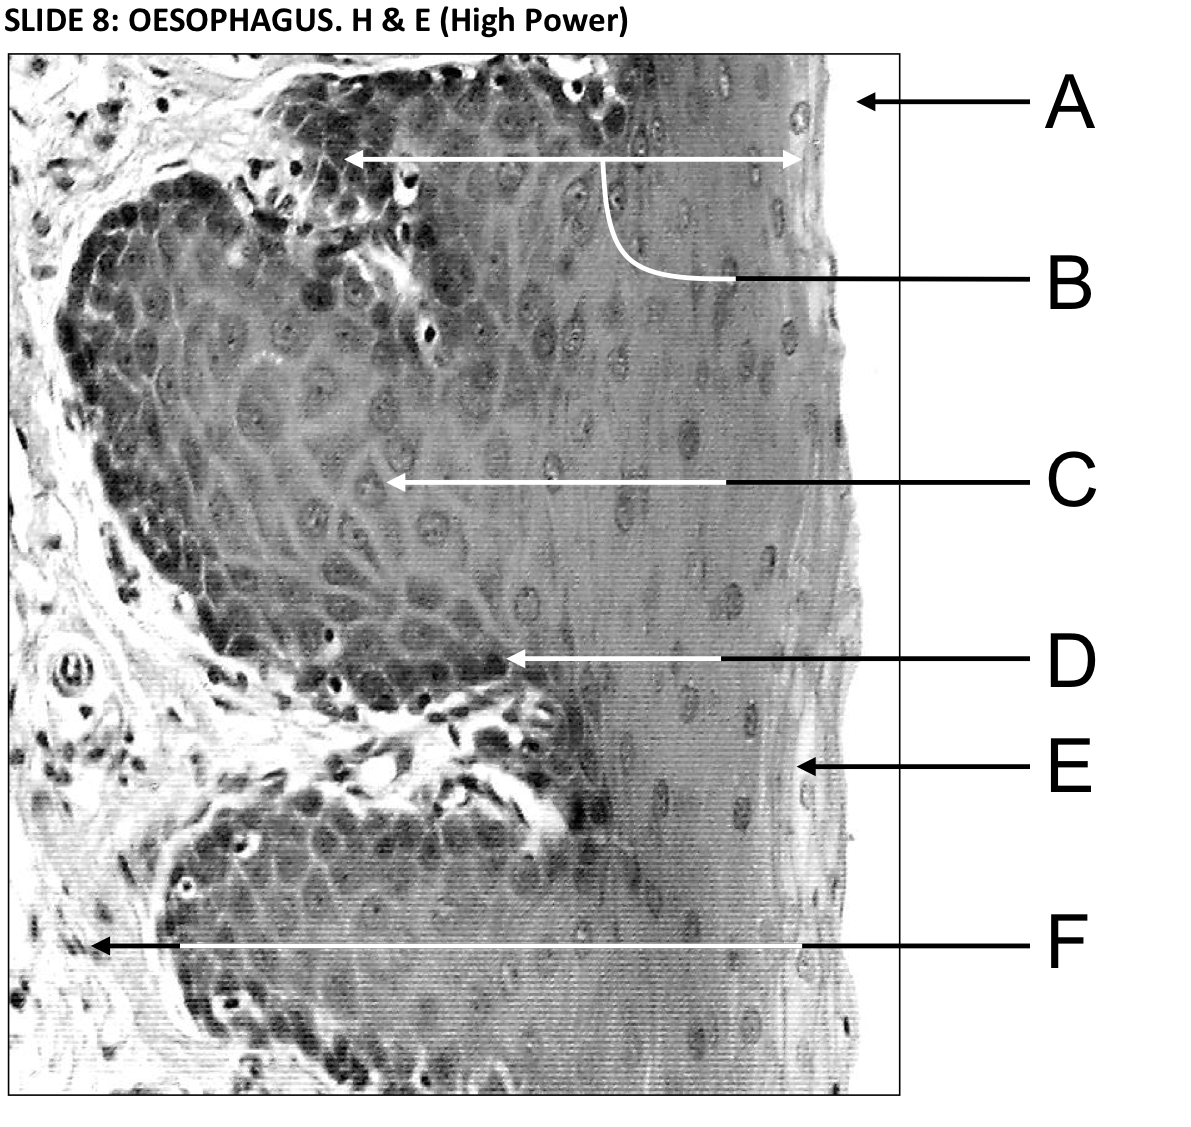

Label the oesophagus

A - Muscularis mucosae (the muscular layer of this mucous membrane complex)

B - Stratified squamous non-keratinised epithelium

C - The oesophageal lumen is convoluted but opens up during swallowing

D - Submucosa - dense fibroelastic connective tissue containing glands

E - Muscularis externa - an outer longitudinal and an inner circular muscle laye. Can be a mixture of smooth and skeletal muscle

A - Oesophageal lumen

C - Cells in the middle of the epithelium are polymorphous (have many shapes)

D - The deepest epithelial cells are cuboidal

E - Cells are squamous (flattened) near the epithelial surface but remain nucleated

F - Lamina propria - looses connective tissue beneath the epithelium. Interdigitation of lamina propria and epithelium reduces the likelihood of shearing